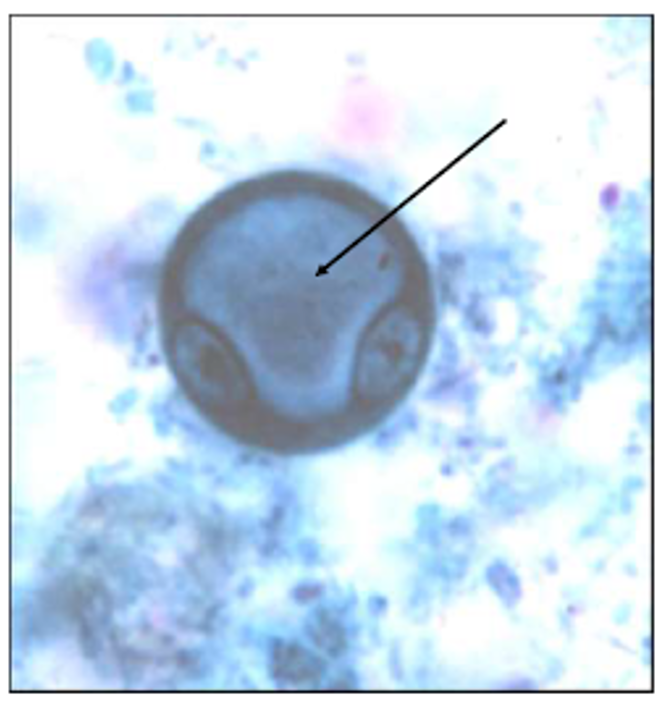

chromatoid body (from: entamoeba histolytica cyst)